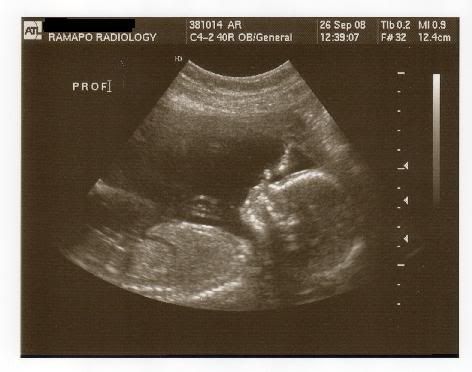

So, everything went very well with my little 's anatomy scan! He was wiggling up a storm. My Mom and Stepdad got to come in and see him too. Every organ and system is developing perfectly and he appears to be happy and healthy with 10 fingers and 10 toes! He's also measuring right on schedule.

So, without further adieu....here's my baby at almost 20 weeks (19 Weeks, 6 Days)